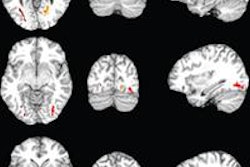

The results showed a significant correlation between high ImPACT total symptom score and reduced fractional anisotropy at the gray-white junction, most prominently in the auditory cortex. Significantly decreased fractional anisotropy was found in patients with sleep-wake disturbances in the parahippocampal gyri relative to patients without sleep-wake disturbances.

The results suggest that the problem facing concussion patients may not be the injury itself, but rather the brain's response to that injury, according to Fakhran. In addition, the neurodegenerative changes are similar to those seen in early Alzheimer's dementia.